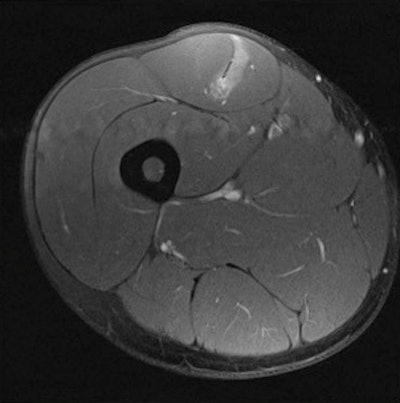

Axial fat-suppressed image demonstrates a muscle tendon junction injury to rectus femoris. Image courtesy of Dr. Steve James.In many cases, MRI scans can identify muscle injuries, but radiologists want to be able to provide an indication of the severity of the injury so the referring clinician can decide how long the athlete needs to refrain from sport to ensure satisfactory healing. Evidence about their ability to provide this information is mixed, according to James.